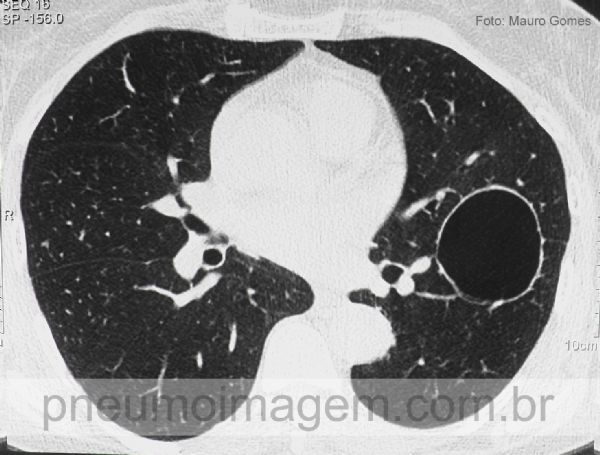

Corte de tomografia de alta resolução com a imagem cística intraparenquimatosa sem conteúdo no seu interior (cisto broncogênico intraparenquimatoso).

Na sua maioria, os cistos estão localizados no mediastino ao longo da árvore traqueobrônquica, mas também podem ser encontrados no parênquima pulmonar ou abaixo do diafragma. Quando os cistos são intrapulmonares, o diagnóstico é mais difícil.